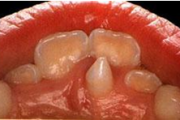

Koonilise kujuga lisahammas ülemiste tsentraalsete lõikehammaste vahel.

Suulaepoolt lõikunud koonilise kujuga lisahammas